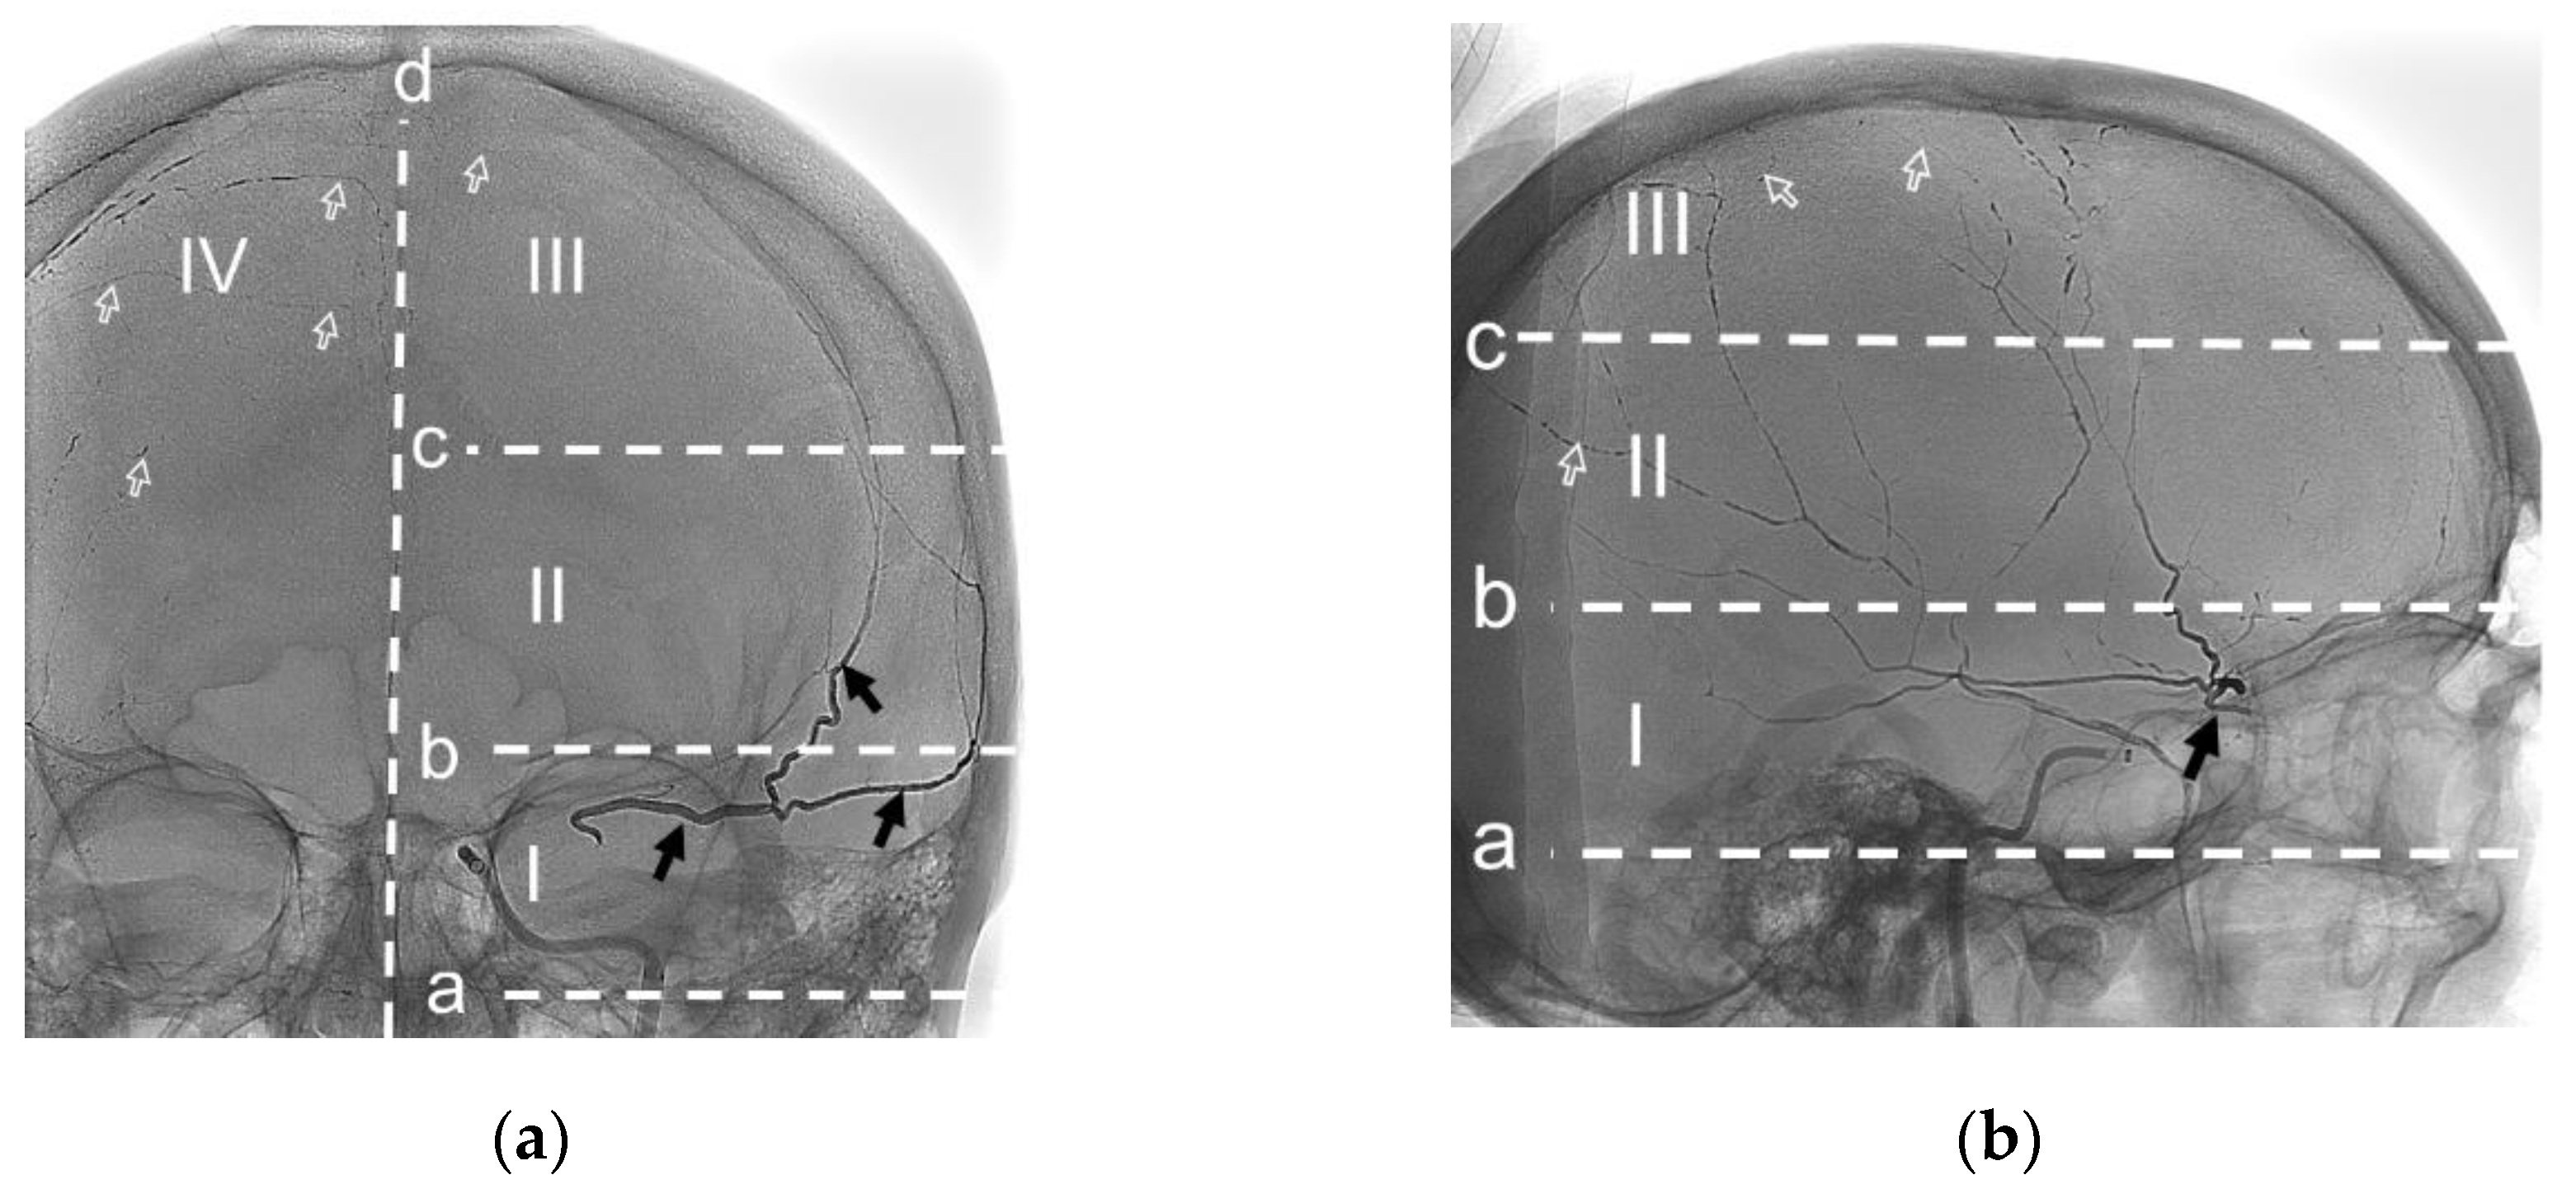

To describe the behavior of NAGLEMs during MMA embolization, the following parameters were evaluated: the level of penetration (Figure 8), microcatheter position, microcatheter diameter, penetration into the dural veins at the first push, assessment of penetration into the dural veins at the end of embolization, the time of embolization, the appearance of extravasation of the gel-like embolic agent and the time of extravasation from the beginning of embolization (Table 4), (Figure 9).

According to the presented table, when comparing of gel-like embolic agent, statistically significant differences were revealed depending on level of NAGLEMs penetration in dural vessels (p = 0.009) (applied method: Pearson’s chi-square test). The diameters of the microcatheters used by both groups were comparable, as were their positions. No significant relationship was found between these parameters and the degree of penetration.

Figure 3. Posterior–anterior (a) and lateral (b) radiographic images show the radiopaque cast in both MMAs (arrows). The black arrows – ipsilateral MMA (left side) with level II penetration by ONYX 18. The white frame arrows – contralateral MMA (right side) with level III penetration by ONYX 18. A – auriculo-orbitalis line; b – supra-orbitalis line; c – median point line. I – proximal, II – lateral, III – parasagittal, IV – contralateral levels of penetration. (Case #1, Refer to section 3.4.1.).

2.6. Analysis of NAGLEMs Behavior During MMA Embolization

For convenience in delineating the gel-like composition penetration level, the Frankfort horizontal plane was used as a basis. The auriculo-orbitalis line passes through this plane in the lateral projection. The second line supra-orbitalis as in the scheme of R.U. Krönlein [45] runs parallel to the line auriculo-orbitalis. The third line was added by us to emphasize the most distal blood supply zone of the ipsilateral MMA; it also runs parallel to the first two lines and through the craniometric Median point. Median point, instrumentally determined on the frontal bone as the greatest elevation from a cord between Nasion and Bregma. Nasion point - intersection of the nasofrontal sutures in the median plane. Bregma point - where the sagittal and coronal sutures meet. The sagittal plane is the main boundary of the vascularization level of the ipsilateral MMA.

Thus, the gel-like composition penetration levels of the ipsilateral MMA can be distinguished as follows:

(1)

Level I is proximal, bounded by the auriculo-orbitalis and supra-orbitalis lines; This level is typically characterised by the origin of the MMA from the maxillary artery and the presence of a large MMA trunk. In accordance with the Adachi classification, as modified by Giuffrida-Ruggeri [46,47,48,49,50], the principal MMA trunk may be subdivided into a frontal and a parietal branch in this region, a characteristic feature of MMA types 2b, 3 and 4. Also at this level, the MMA may have the most dangerous anastamoses with the ophthalmic artery and the tympanic branch of the MMA[2,40,42,51].

(2)

Level II is lateral, bounded by the supra-orbitalis and a line through the craniometric Median point; At this level in MMA types 1 and 2a (according to Adachi in the Giuffricla-Ruggeri modification [46,47,48,49,50]), there is a distinction between the main trunk of the MMA, which is divided into frontal and parietal branches. In this region, second- and third-order branches connecting the frontal and parietal branches of the MMA can frequently be observed[2]. Additionally, in this region, the parietal branch often connects to the posterior meningeal artery, which represents a significant anastomosis with the vertebral artery system.

(3)

Level III is parasagittal, limited by the line through the craniometric Median point and sagittal plane; At this level, branches are connected with the arteries of the walls of the superior sagittal sinus, and there are direct anastomoses with the anterior circumflex artery and, respectively, with the ophthalmic artery [2].

(4)

Level IV – is contralateral for its ipsilateral MMA, Level IV is characterized by collateral connections with the contralateral meningeal arteries and Falx vessels.

The evaluation scheme according to the outlined protocol is shown in Figure 3. The penetration of the embolic agent into the dural veins, as well as the time and the occurrence of extravasation of the embolic agent during embolisation, were considered separately. The results of the evaluation can be found in section 3.3.

A 51-year-old man, suffered a head injury with loss of consciousness 4 months ago, did not seek medical attention. A week before the operation the patient developed motor aphasia, CT scan of the brain revealed a chronic subdural hematoma compressing the left cerebral hemisphere, maximum thickness 26 mm, midline shift 9 mm. MMA embolization was performed using ONYX 18. During embolization it was not possible to achieve distal penetration of the MMA branches on the ipsilateral side, so we had to perform embolization on the contralateral side to ensure penetration of the embolic agent through the midline.

The behaviour of the gel-like composition and its penetration level were evaluated according to the above protocol in section 2.6. (Figure 3).